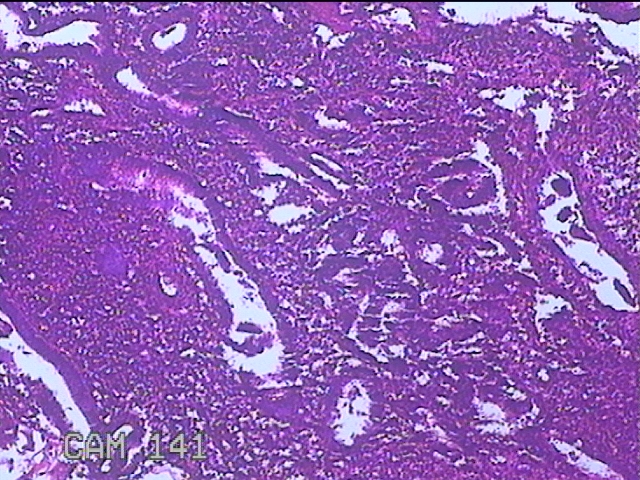

宫腔内容物

性别

女

年龄

30岁

临床诊断

1)异常子宫出血 2)子宫内膜息肉 3)宫内节育器

一般病史

间断性阴道流血后半年余。

标本名称

大体所见

灰白暗红色不规则碎组织2.5x1.8x0.8cm一堆。

图1